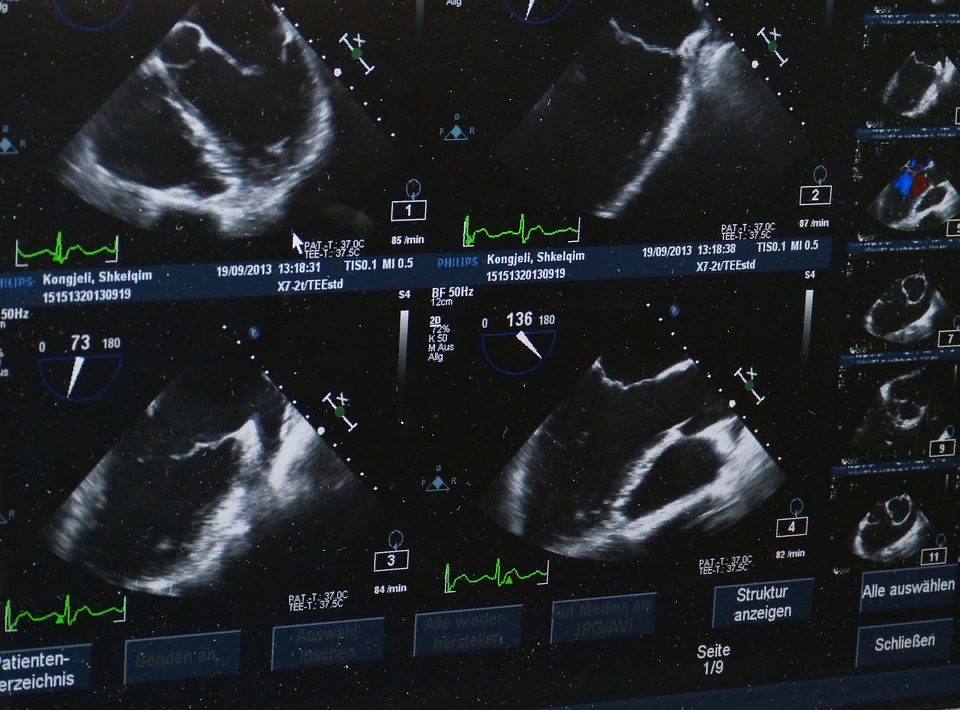

Гипертрофию миокарда левого желудочка в обычной клинической практике можно заподозрить с помощью осмотра пациента и электрокардиографии, а подтвердить это состояние помогает УЗИ сердца.